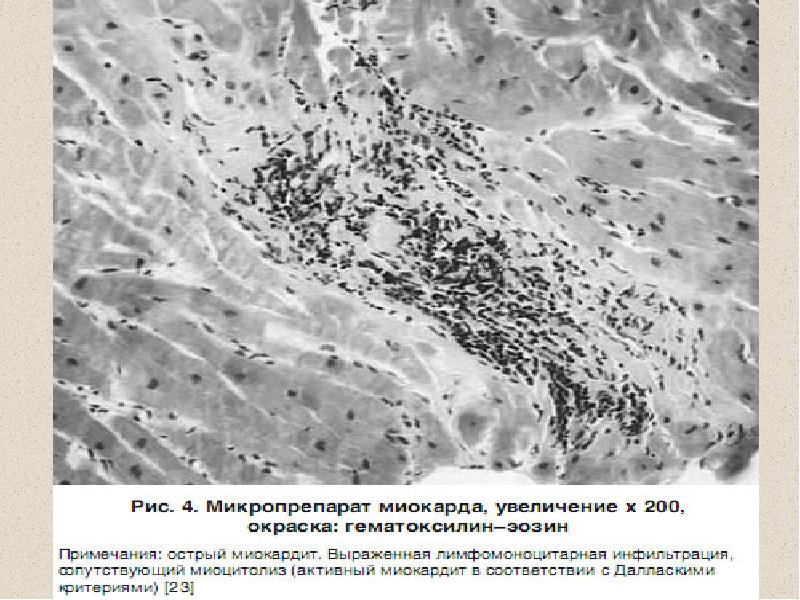

Межуточный миокардит: гистологические исследования